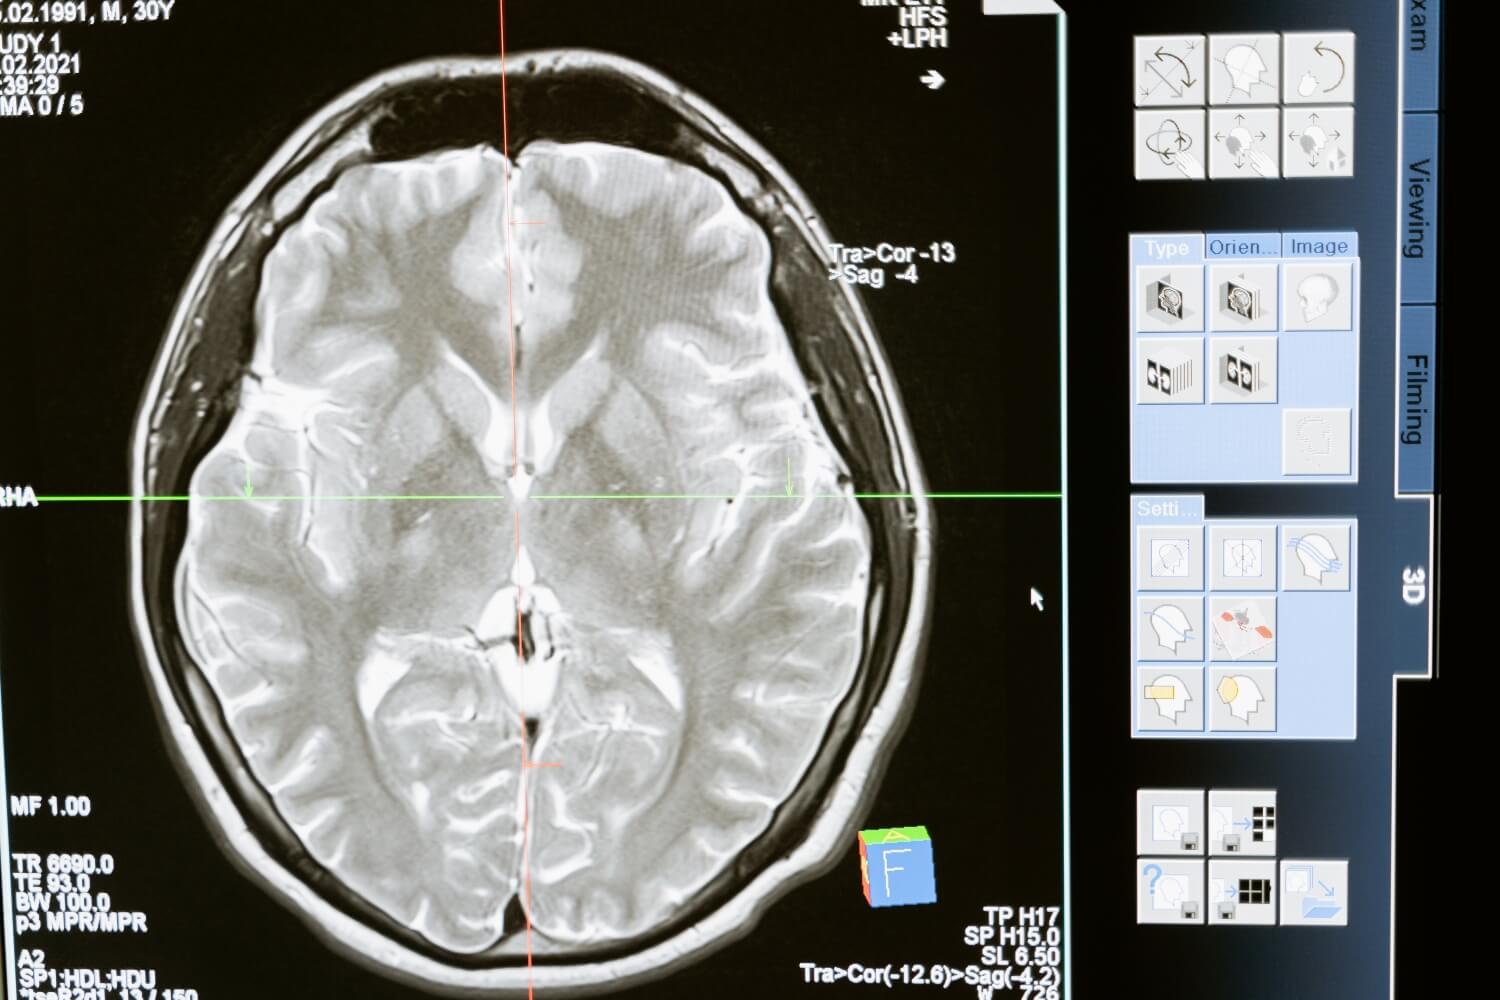

뇌졸중은 뇌에 혈액을 공급하는 혈관이 막히거나 파열되어 뇌 기능에 영향을 미치는 상태입니다. 뇌졸중, 뇌혈관 질환 및 뇌졸중은 모두 같은 것이며 뇌졸중에는 두 가지 주요 유형이 있습니다. 첫 번째는 뇌혈관이 막혀 혈액이 뇌로 원활하게 흐르지 않아 뇌의 일부가 손상되는 뇌경색이고, 두 번째는 뇌혈관이 터져 손상을 일으키는 뇌출혈이다. 국내에서는 뇌졸중의 약 85%가 뇌출혈 환자보다 더 자주 발생하는 것으로 알려져 있다.